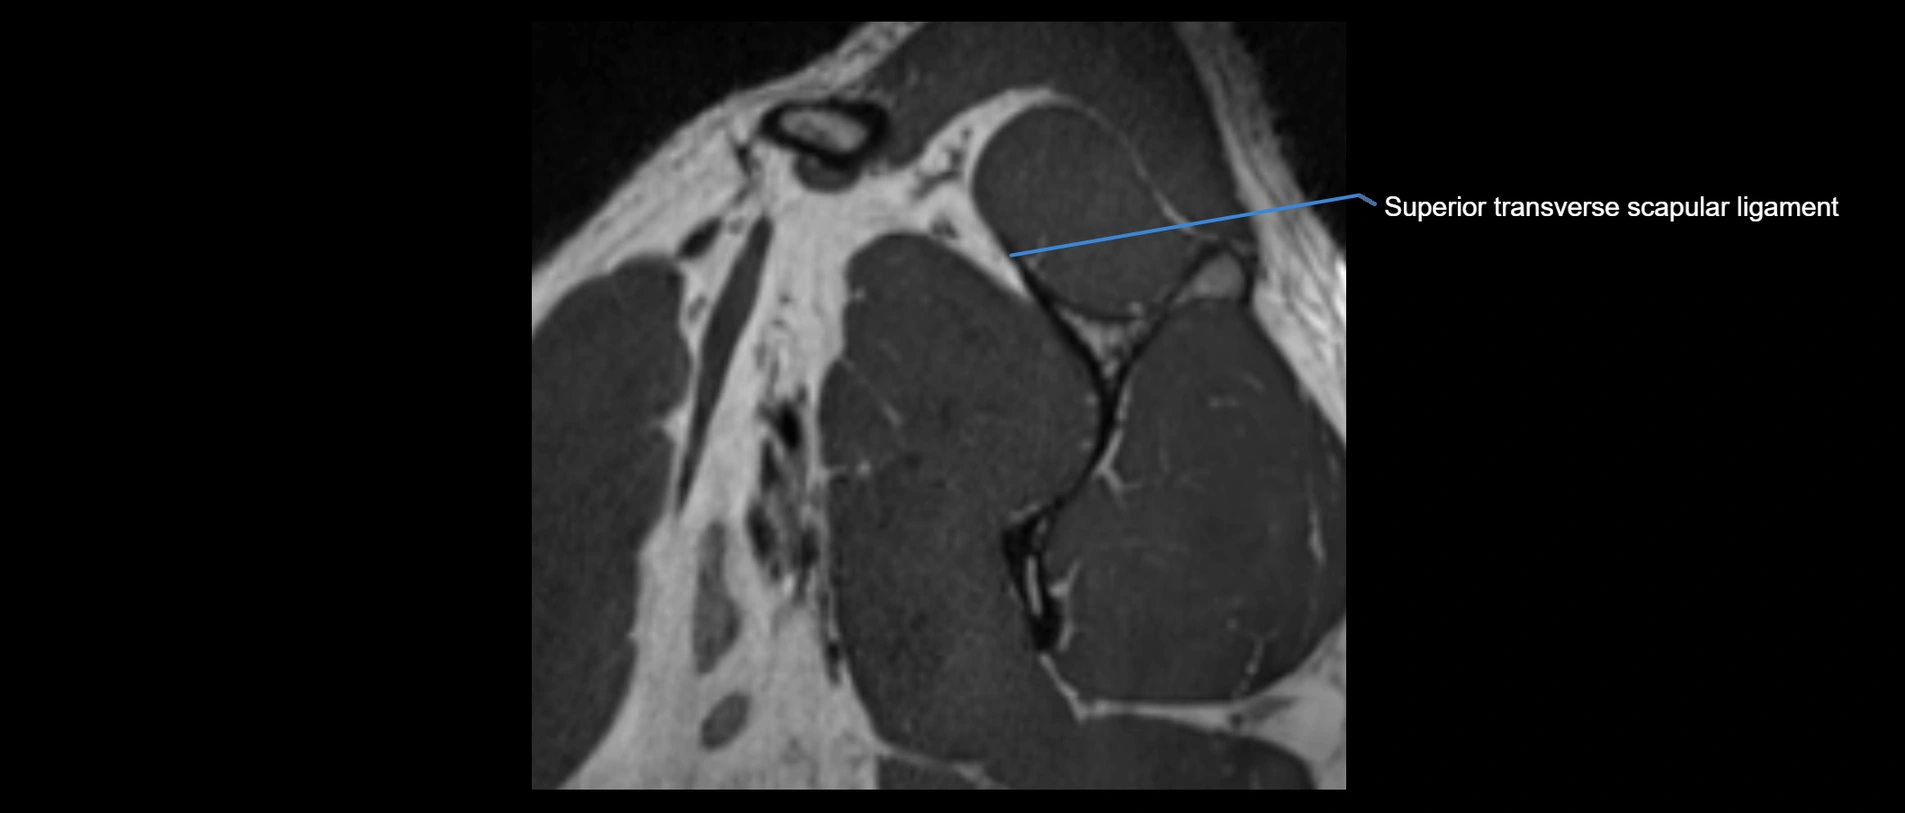

MRI images

image